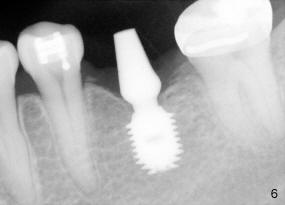

The tooth #19 has been lost for 8 years with tilting of #18 (black line in Fig.1). A 6x8 mm Bicon implant (3 mm post) was placed as distal as possible (I in Fig.2). Three months later, the implant was uncovered with evidence of osteointegration (arrowheads in Fig.3). A 4x6.5 mm 0 degree non-shouldered abutment with 3 mm post (A) was inserted into the implant well. The flat surface of the abutment needed to face distal in order to seat the abutment without interference. The implant/abutment complex was used as an anchorage to upright #18. The tooth #17 was extracted prior to orthodontic treatment (compare Fig.5,6 vs. 1-3). A bracket was bonded to Jet temporary crown of #19 and open coil spring was placed between #18 and 19. In the first two months, distalization of #18 is limited (between black and white lines in Fig.4), partially due to the fact that the bracket of #19 was debonded quite easily. A premolar band (B in Fig.5) was cemented to the temporary crown of #19. In another two months, the tooth #18 was pushed to desired position (arrowhead) under the tension of open coil spring (*). The mesial crest height of #18 was increased during uprighting (arrow, as compared to Fig.1-3). A new temporary crown was fabricated to fit the enlarged space of #19 with cementation of a molar band. The next problem is that the new molar temporary crown was easily dislodged from the 4x6.5 mm abutment even with a permanent cement. A larger abutment (5x6.5 mm) was used (Fig.6), with relining the temporary crown. The upper end of the larger abutment has sharp edge (Fig.8: white arrowhead, as compared to rounded edge of the smaller abutment (Fig.7). This may also contribute to better retention. In another 3 months, the temporary crown was dislodged again. An even larger abutment (6.5x6.5 mm with two flat surfaces (blue arrowheads in Fig.9) was adopted.